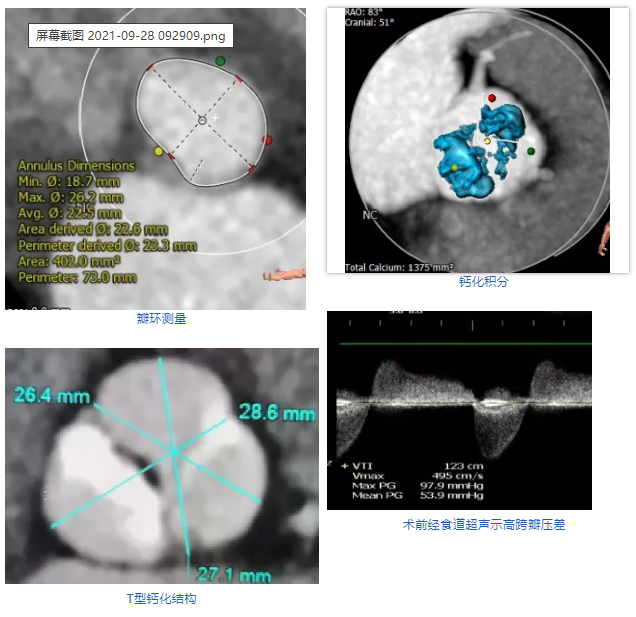

患者女性,75岁,因“反复胸闷、胸痛1年余”入院。超声心动图示主动脉瓣重度狭窄钙化,伴中重度关闭不全。CT显示主动脉瓣为Type 1型二叶瓣,且无冠瓣与左右冠瓣融合嵴形成“T型”钙化结构,属TAVI挑战病例。瓣环平均直径22.5mm,瓣环面积402.0mm²。左冠脉开口高度11.8mm,右冠脉开口高度11.0mm。术前TEE示峰值流速4.9m/s,平均跨瓣压差54mmHg,有强烈手术指征。

术前心脏彩超                               术后心脏彩超